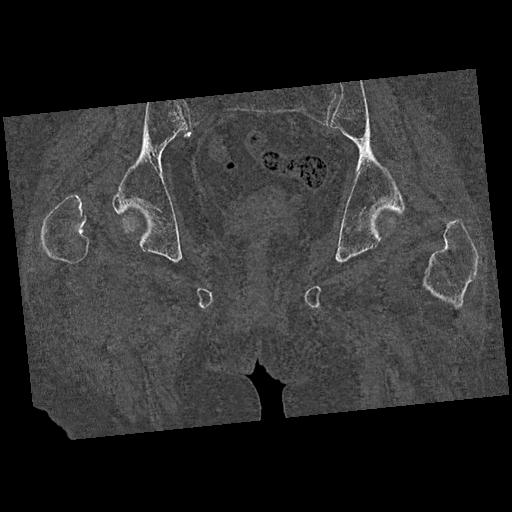

100703 1/27 両股正面+軸 1/29 両股正面+軸 94歳女性 パンソンロン

46666 1/28 両股正面+軸と 1/26 右手関節 2R 76歳女性 右転子部骨折

37 1/18 両股正面+軸 1/22 2R 86歳女性 右転子下

91569 3/25 両股正面とラウエン 70歳女性 人工骨頭+バンクーバー